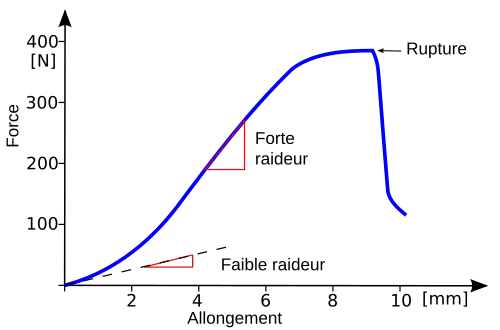

Pour des forces de tension faibles, la courbe a une faible pente (faible raideur), parce que le tendon s'allonge sans augmentation de la force à l'intérieur. Pour une charge plus forte, la résistance augmente. Puis l'accroissement devient en gros linéaire avec une pente plus forte (raideur plus grande). Dans ce domaine, les faisceaux de fibres de collagène du tendon, alignées parallèlement, sont encore élastiques. Pour une tension encore plus forte, des transformations irréversibles ont lieu dans le tendon, qui ne reviendra pas à sa longueur initiale si on le relâche. Quand la force augmente encore, des faisceaux de fibres se rompent isolément (la courbe devient horizontale). Comme toutes les fibres ne sont pas soumises aux mêmes efforts, l'allongement peut encore croître à force constante (la raideur diminue). Quand la raideur s'annule, le tendon se déchire d'un seul coup, ce que l'on voit par la chute brutale de la courbe[7].